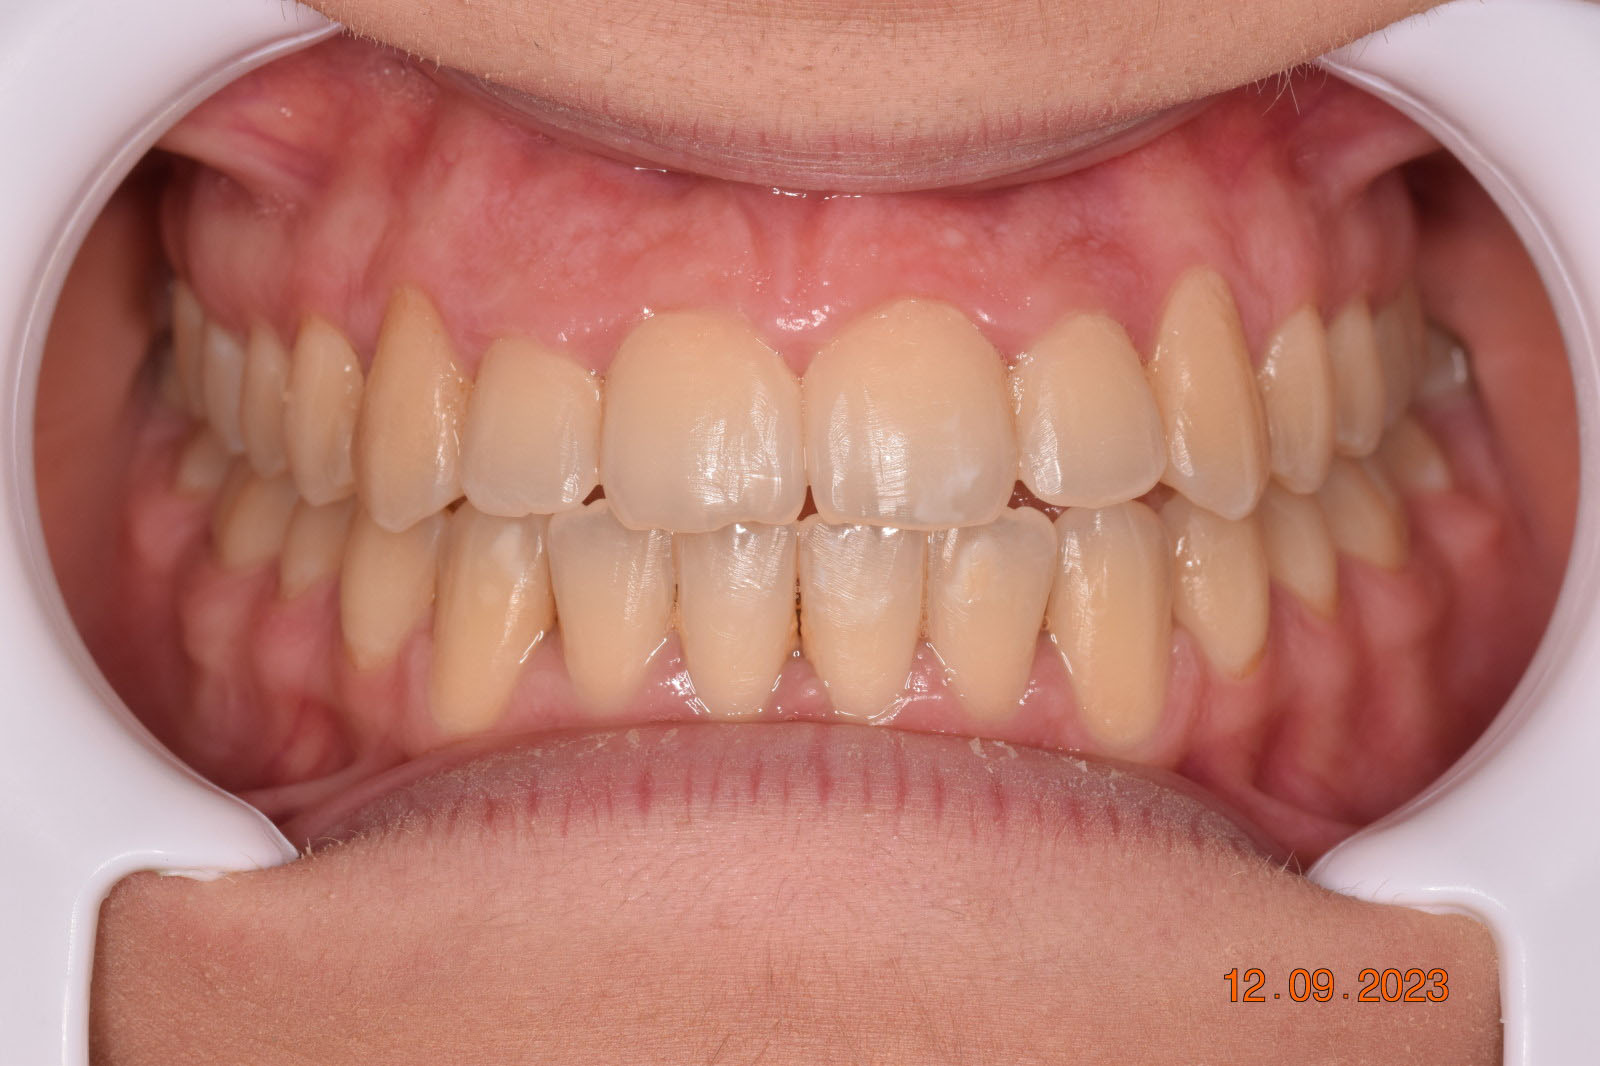

This case posed challenges in all three spatial dimensions, compounded by significant crowding. The patient was highly compliant and maintained excellent oral hygiene throughout the 5.5 years of treatment, which required more than 30 clinical appointments.

The facial changes are impressive considering treatment involved only conventional orthodontics and not orthopedic interventions, TADs, or surgery.

Dr. Coca concludes that improved biomechanical understanding of extreme crowding and torque management could have reduced treatment duration. From his experience, proper force management can facilitate bone remodeling, challenging the idea of bone limitations in orthodontics.

Correcting muscle behavior during swallowing and in the passive state is key to solving open bite and crossbite as well as ensuring lasting stability of treatment outcomes.

Dr. Coca believes that with his current experience and insights, he could have completed the case within three years.

This case was a learning moment for Dr. Coca, reshaping his understanding of low-force, low-friction orthodontics (also known as Damon Philosophy) and highlighting the power of myofunctional therapy in achieving optimal treatment outcomes.